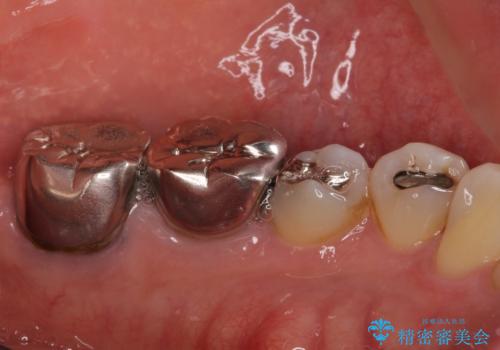

部分矯正を併用した奥歯のインプラント補綴治療

- 奥歯を他院で抜歯した後、インプラント治療を希望とのことで来院された患者様です。

ブリッジの支台を抜歯したことで2本のインプラントが必要であり、その後方はインプラント埋入に必要な骨量が不足していたため、上顎洞粘膜の挙上を行うこととしました。

また、残っている最後方歯は手前に倒れてきていたため、部分矯正により奥に移動させてから、インプラント埋入を行うこととしました。

部分矯正期間中はアンカースクリューやフック、ゴムなどが粘膜にあたり、大変な思いをすることになりましたが、そのおかげでインプラント補綴した歯と最後方歯の位置が非常に良好となり、まるでご自身の歯のように咬むことができるようになりました。